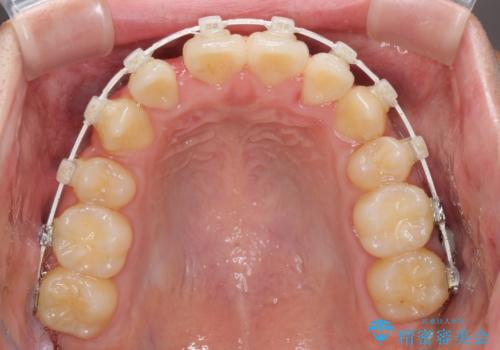

- 矯正装置

- 審美装置

- 2年10ヶ月

- 10-30回